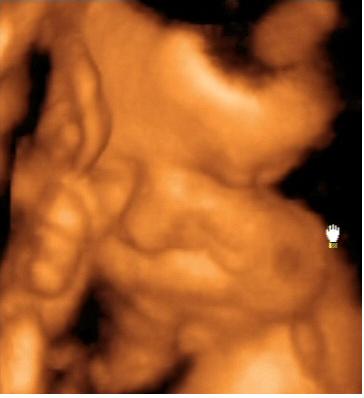

A lényeg. Lányunk lesz. Bár számomra ez nem volt egyértelmű a kép alapján...talán nektek az lesz. Már most kész óriás, 2703 g. Gyönyörű babó, bár most nem voltunk olyan szerencsések, mint a múltkor és folymatosan eltakarta magát. Nagyon fájt a szívem amikor láttam, hogy mennyire össze van "hajtogatva" szegénykém. a bal lába a homlokánál van :(. No de ez van. Remélem azért nem annyira rossz neki.

Küldöm a képeket is.

Nekem egyértelmű a nunika!:)

De jó,és nagyon jók a képek!Örülök,hogy a vágy is teljesült,és kislány lett!

Gratula a lánykához! Ne aggódj, ő abban a pozícióban érzi jól magát! És egyébként is olyan lányos arca van...és milyen pici és széles kis orra. :) Egyébként ahogy Doren is írta, én is elcsodálkozok, amikor Peti elnyújtózik, hogy hogy a fenébe fért el bennem...